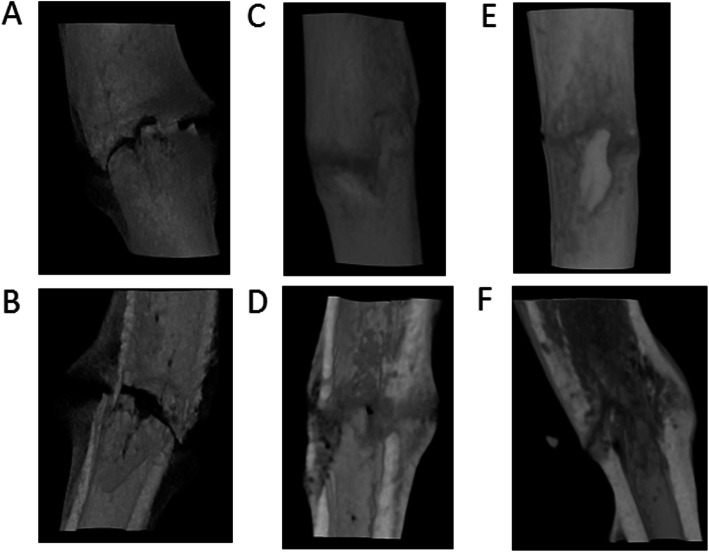

Micro-CT

We obtained three-dimensional micro-CT reconstructed images at the same points with the radiographs taken at 2, 4, 6, and 8 weeks after fracture. Typical examples are shown in Figs. 3 and 4. The fracture gap of the control group’s tibia formed abundant calluses at the fracture end and was not bridged completely at 2 weeks (Fig. 4a and b), but the fracture gap had disappeared at 4 weeks and was bridged by new bone formation (Fig. 4c and d). At 6 weeks, the callus had been reconstructed, and its density was similar to that of the cortex. The non-union of the fracture in the non-union group had persistent fracture gaps throughout all periods. Although a small number of calluses formed, they failed to cross the fracture site to form a bone bridge (Fig. 5a-f).

Fig. 4.

Three-dimensional micro-CT reconstructed images of the control group. The images were obtained at 2 weeks (a), 4 weeks (c), and 6 weeks (e) after surgery and these were viewed by cutting through the long axis of each tibia in the coronal planes (b, d, and f). The fracture gap at 4 and 6 weeks had disappeared and was bridged by new bone formation (e and f)

Fig. 5.

Three-dimensional micro-CT reconstructed images of the non-union group. The images were obtained at 2 weeks (a), 4 weeks (c), and 6 weeks (e) after surgery and these were viewed by cutting through the long axis of each tibia in the coronal planes (b, d, and f). The non-union group tibia persisted as fracture gaps throughout all periods (b, d, and f). As time went on, bone absorption widened the fracture gap